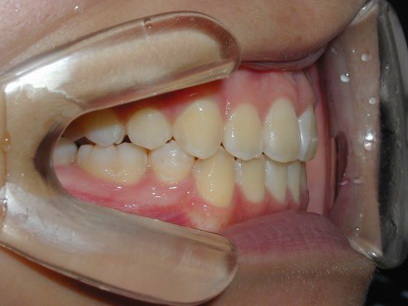

永久歯に交換するためのスペース不足による前歯のガタガタで、取り外しができる拡大床にて上下顎の幅を拡大した後、上顎の前歯をマルチブラケット装置で並べました。治療の期間は1年9か月でした。

終了時